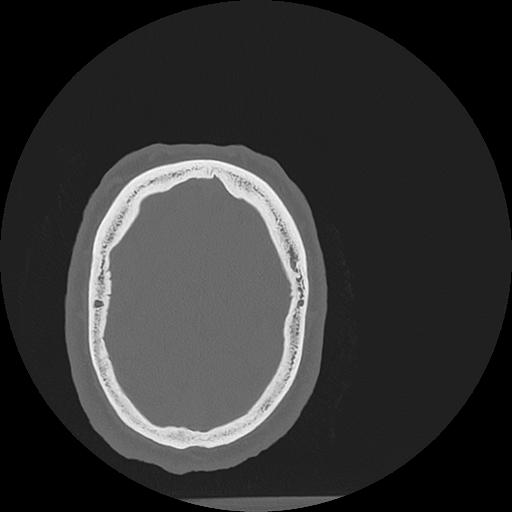

7 HUESO,,Vol,0.5,HUESO,,